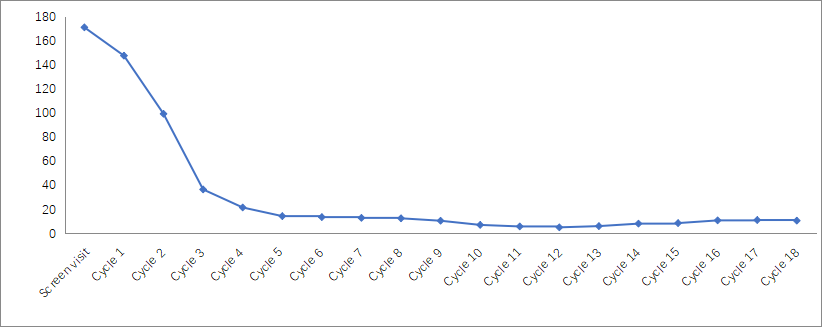

1. AFP值变化

用药后3个月AFP明显下降,用药10个月后AFP降至10 ng/mL以下,详见图1。

图1. AFP水平变化